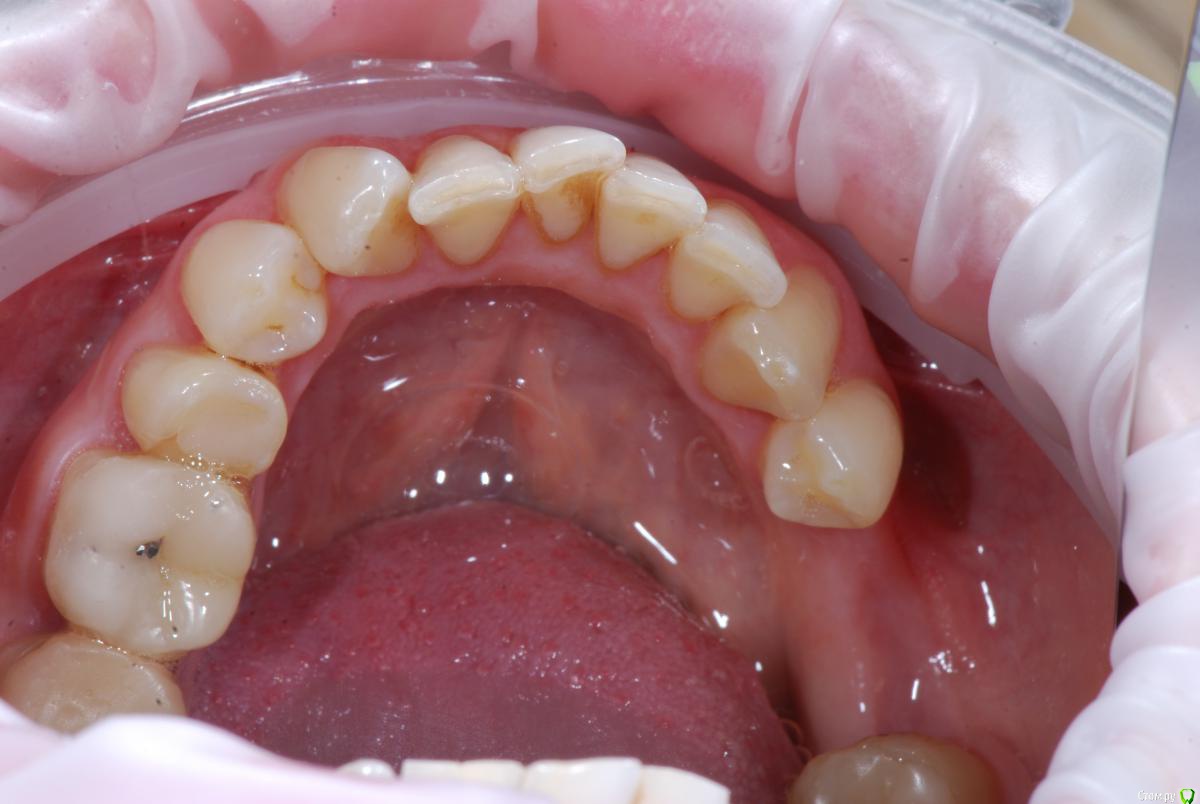

krokomot Опубликовано 12 декабря, 2016 Поделиться Опубликовано 12 декабря, 2016 Вот именно в чем в принципе сомневаетесь? и на моделях надо указывать анатомический центр, тогда сразу понятнее станет чего и куда и на сколько. Ссылка на комментарий

Afffinity Опубликовано 13 декабря, 2016 Автор Поделиться Опубликовано 13 декабря, 2016 Вот именно в чем в принципе сомневаетесь? и на моделях надо указывать анатомический центр, тогда сразу понятнее станет чего и куда и на сколько. ну Вы хотя бы свои мысли озвучили бы, расчет трг, характер асимметрии (в каком положении головки, что на КТ?) ... полностью Вам не распишут план, вопросы более конкретные попробуйте задать для коллегЕсли кратко то по расчетам ТРГ 2й скелетный класс, в цифрах завтра распишу. Прошу прощения что сразу не выложил. 2е, смущает смещение центральной линииПланируем установить систему Damon Q. Самый главный вопрос, возмножо ли в данном случае обойтись без удаления премоляров? Ссылка на комментарий